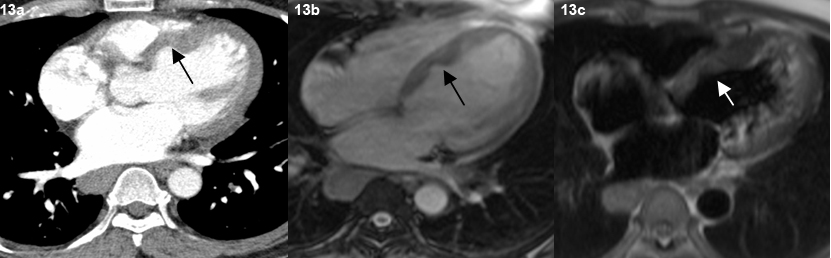

End stage lung disease was seen in three patients with presence of fibrosis, reticulation and traction bronchiectasis [Table/Fig-12]. Cardiac sarcoidosis with focal thining and bowing of the interventricular septum was seen in one patient which was subsequently confirmed on MRI [Table/Fig-13,14]. No patient had evidence of pleural effusion, pleural plaques or pleural calcification. No cavitatory lesions were seen. No patient in this study had any upper abdominal pathology in the visualised images.

Representative axial contrast enhanced CT scan image in mediastinal window (a), TRUFI (b) TIRM (c) MR images shows thinning and bowing of the interventricular septum towards the right side (arrow).

One patient was found to have focal thinning and bowing of the interventricular septum. Cardiac MRI showed delayed endocardial enhancement, features consistent with cardiac sarcoidosis. However, similar enhancement can be seen in other forms of myocarditis [20]. The patient also had the classical nodules in a perilymphatic distribution in the lung parenchyma.